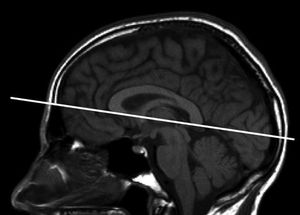

Orientation of axial oblique sequences for MR imaging of the brain. Orientation of axial oblique sequences should be along the subcallosal line as indicated by the solid line.